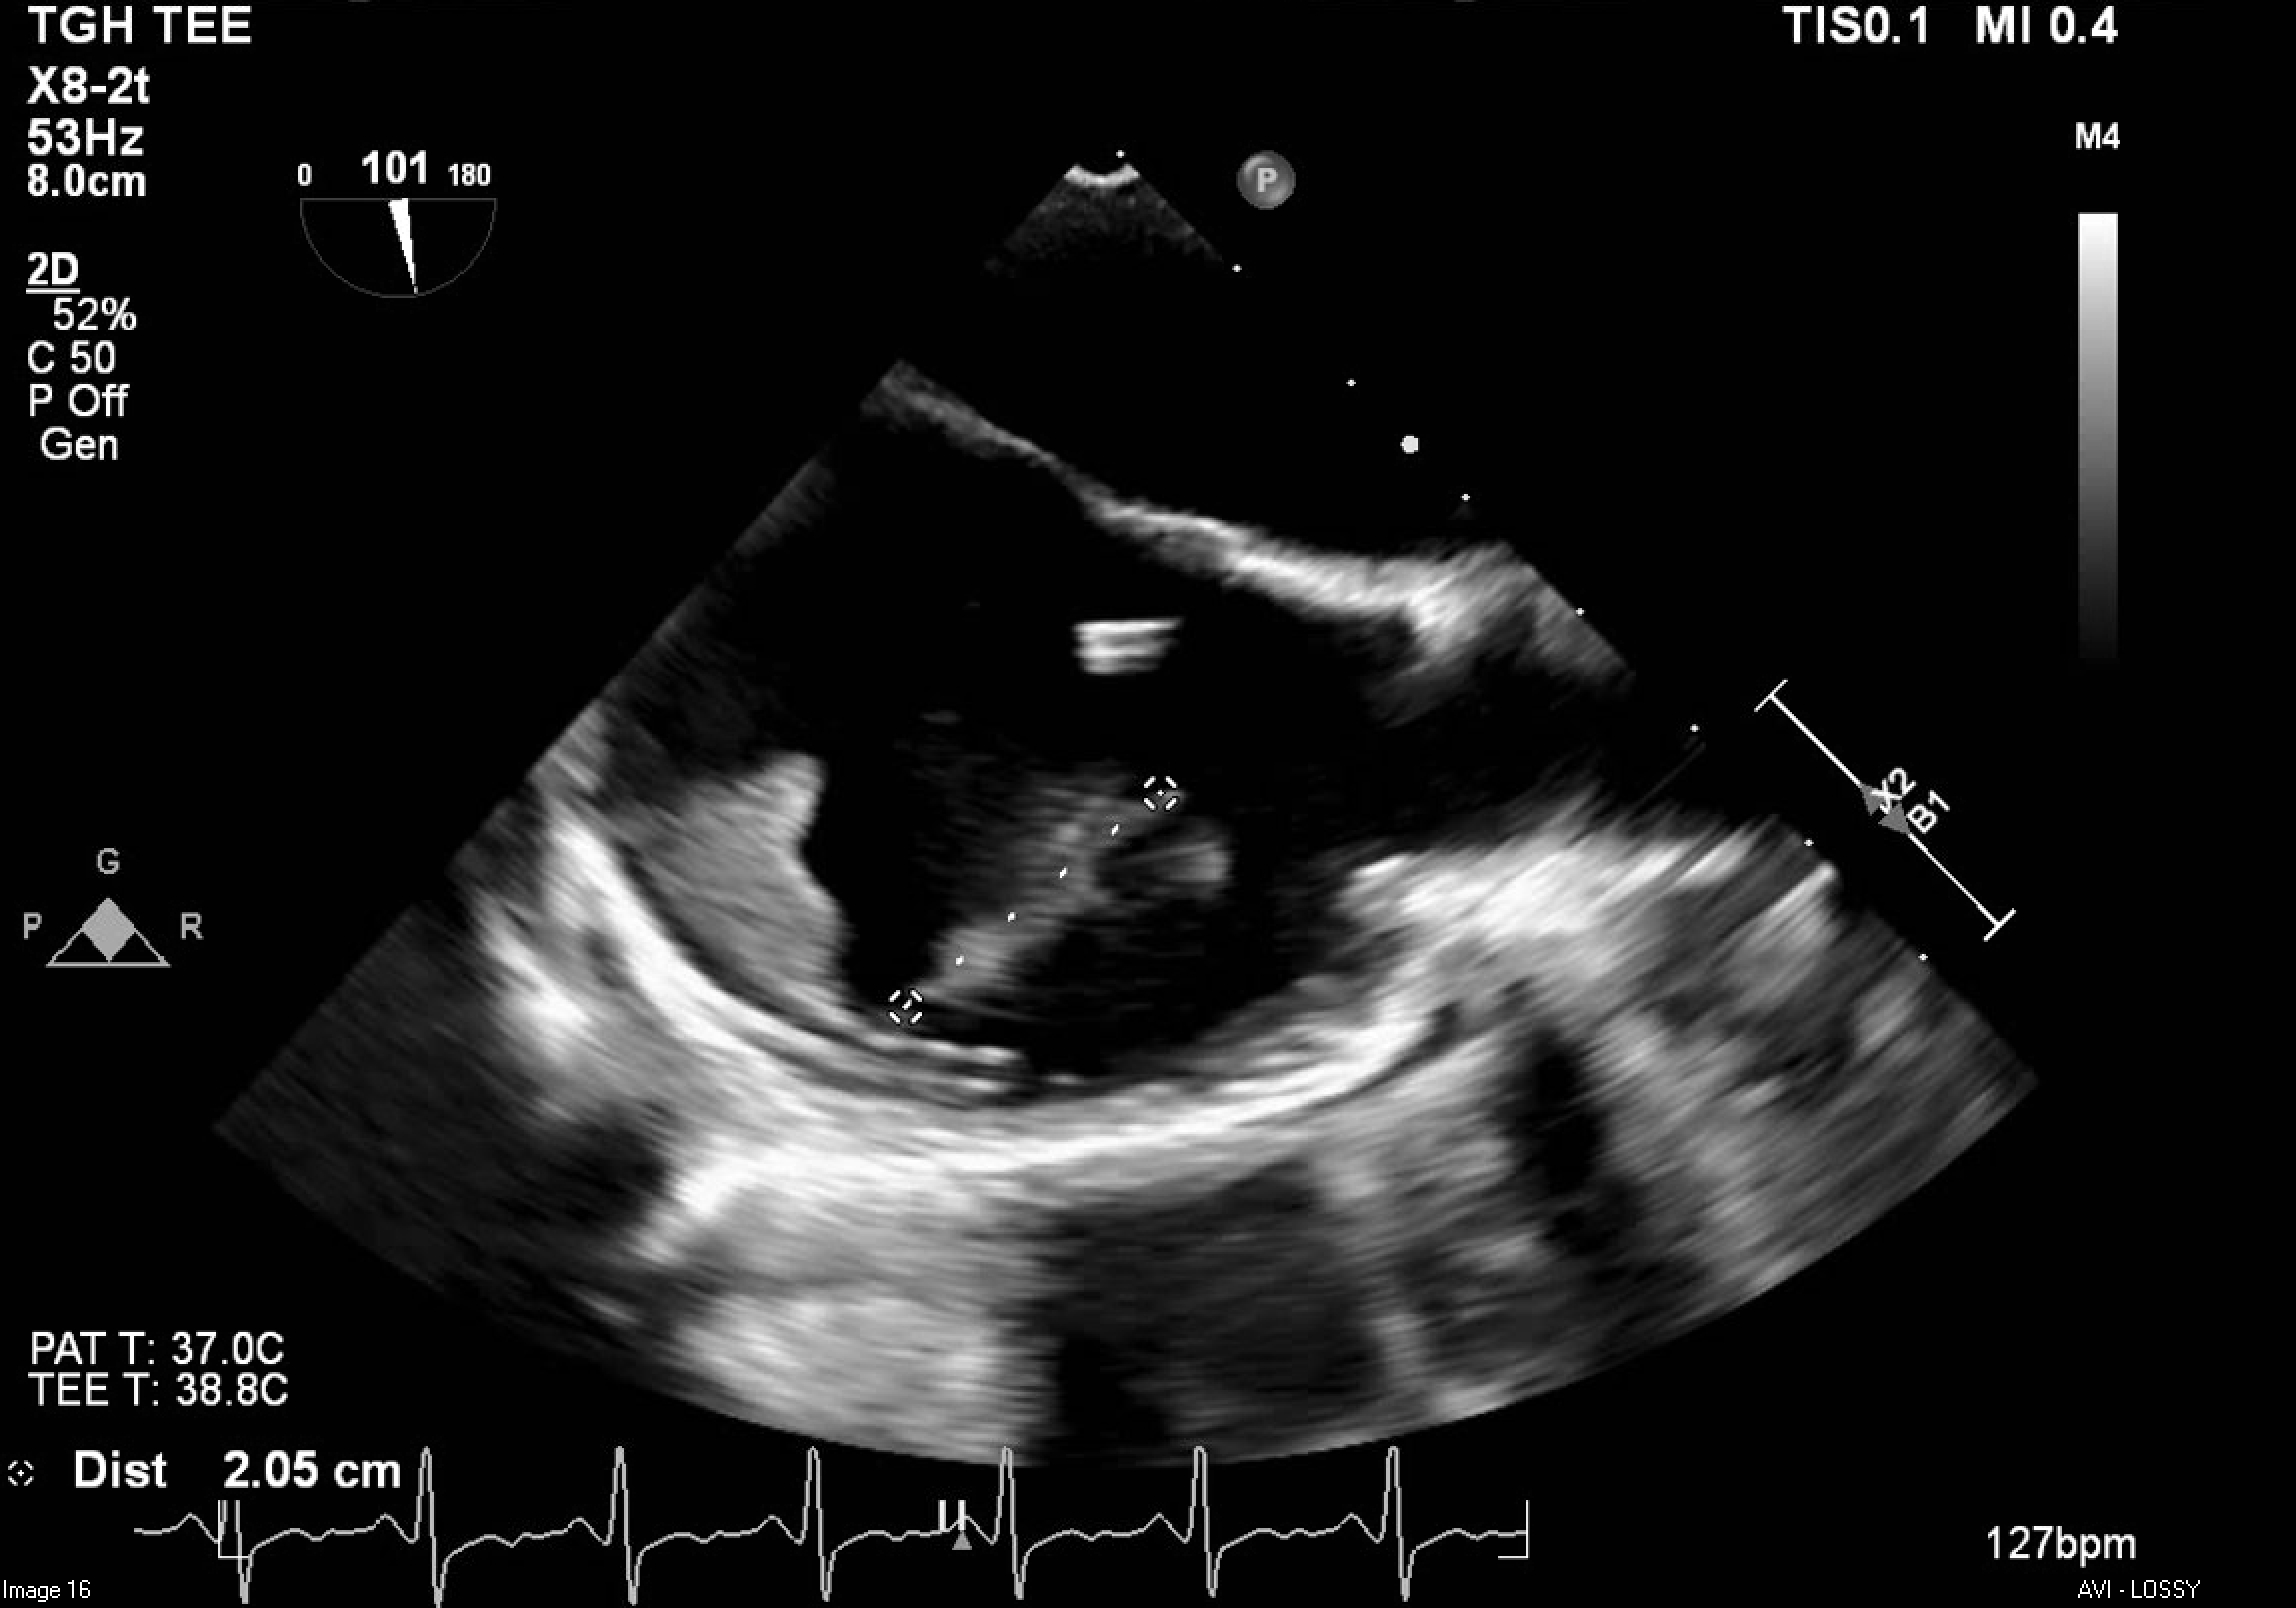

A 27-year-old female with recurrent fevers, arthralgias, an evanescent rash, and hyperferritinemia (10,661 ng/mL) was diagnosed with AOSD following an initial presentation of macrophage activation syndrome (MAS). She improved with anakinra and corticosteroids. Months later, she was readmitted with fever and hypotension requiring vasopressors. Infectious workup was negative, and recurrent MAS was diagnosed. Transthoracic echocardiography revealed severe PH and a mobile right atrial thrombus, initially suspected to be central-line associated; the central line was subsequently removed. She responded to intensified immunosuppressive therapy. Days later, she developed headaches and seizures. Brain MRI showed posterior vasogenic edema concerning for posterior reversible encephalopathy syndrome (PRES), likely related to immunosuppression. Her condition rapidly deteriorated with severe headache and bilateral fixedly dilated pupils. Imaging revealed bilateral cerebellar infarctions with hemorrhagic conversion and tonsillar herniation, prompting emergent suboccipital craniectomy and external ventricular drain placement. A follow-up transesophageal echocardiogram identified two large (>2 cm) right atrial thrombi, one highly mobile, indicating persistent thrombosis despite line removal. Agitated saline contrast confirmed a patent foramen ovale with right-to-left shunting.

Given recent intracranial hemorrhage, anticoagulation was contraindicated. Due to the risk of embolization and obstruction, she underwent successful percutaneous AngioVac-assisted thrombectomy. She was also treated with emapalumab targeting interferon-γ to control systemic hyperinflammation.